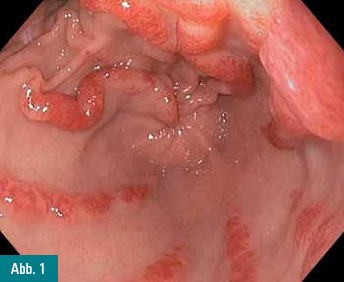

In der jetzt wieder durchgeführten Gastroskopie finden sich im Antrum

wieder hochgradige streifige Rötungen (Abbildung 1&2).